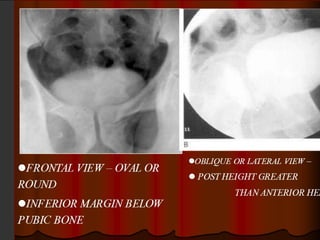

The balloon on a string

sign This sign refers to the

appearance of a high and

somewhat eccentric exit

point of the ureter from a

dilated renal pelvis and is

a typical finding of

ureteropelvic junction

obstruction

PUJO